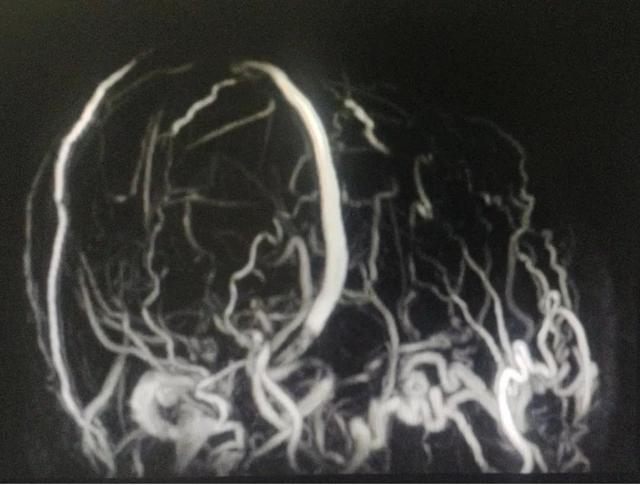

头颅MRV提示颅内静脉系统异常,窦汇、双侧横窦、乙状窦缺如,大量增生粗大引流静脉。头颅MRI未提示脑实质肿胀、梗塞、出血等表现。